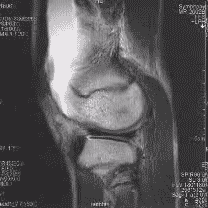

ام آر آی

- در مقایسه با سی تی اسکن, ام آر آی شکستگی های استخوانی را بخوبی نشان نمی دهد.

- در مقایسه با سی تی اسکن, ام آر آی برای بررسی رباطها و تاندونها بسیار عالی است.